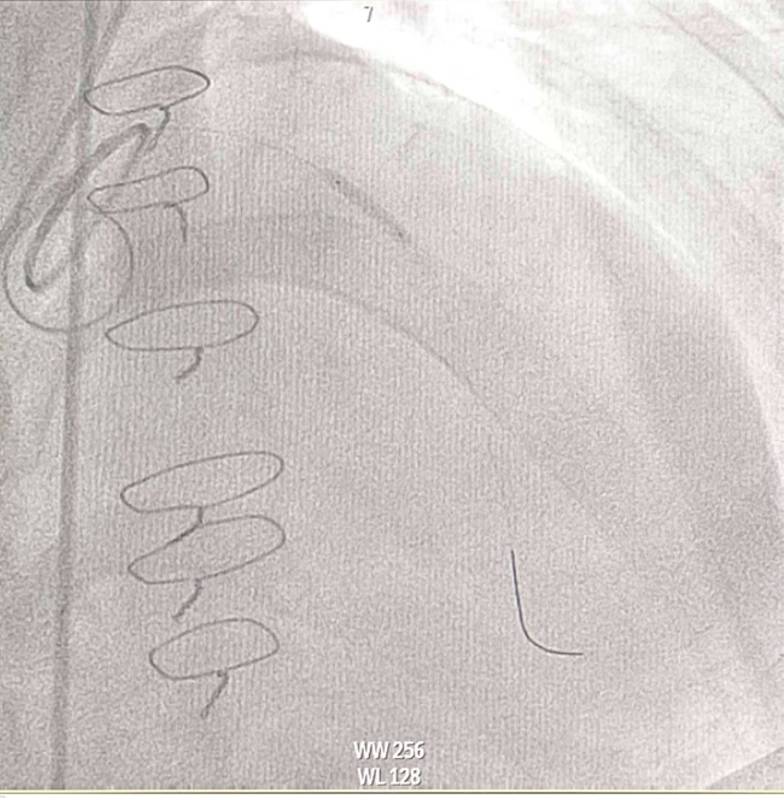

CAG was performed with right femoral approach with JL 4.0/7 Fr, JR 4.0/6 Fr diagnostic catheter showedRight dominantLM : mild irregular, non significant stenosis.LAD : total occlusion mLAD.LCx : mild irregular, non significant stenosis.RCA : non significant stenosis.

Inserted Sion wire and thrombuster to LAD revealed multiple red clots.SC balloon 2.0 x 15 mm, then 2.5 x 15 mm, was inflated at mLAD up to 12 atm. IVUS insertion to LAD revealed vessels’ size LM 5-5.5 mm, pLAD 4-4.5 mm, mLAD 3-3.5 mm with intraluminal thrombus, dLAD 2.75-3 mm. Multiple inflations were done at mLAD with SC balloon 2.5 x 15 mm. After multiple SC balloon inflations, the CAG revealed slow flow phenomenon. Then, the operator performed thrombus aspiration, multiple SC balloon 2.0 x 15 mm inflation and gave IC integrillin 3.4 ml. The final angiogram was acceptable result. The anticoagulant was given after CAG. Chest pain was subsided and hemodynamic parameters remained stable. EKG recorded after angiography showed resolution of ST elevation at V1-3. Later, the patient was discharged with warfarin. The Aortomitral intervalvular fibrosa repair surgery was planned due to embolic complication.